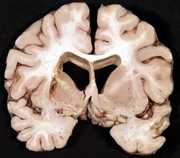

11